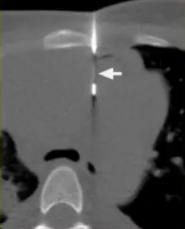

在CBCT成像下的肺病变活检与以前的PET-CT融合

CBCT+PET-CT图像融合引导下活检的操作步骤

1. 将先前获得的PET-CT扫描被导入工作站。

2. PET-CT扫描图像与CBCT图像配准融合

配准包括手动识别两个数据集中的同源地标,然后通过平移和/或旋转对它们的对齐进行优化。

3. 基于融合的PET-CBCT数据,计划穿刺针路径指向PET-高代谢的目标

4. 基于这一计划,活检针被定位在实时反馈与目标解剖和配准代谢活动的关系。

5. 使用相同的成像融合方案获得CBCT数据来确认针的定位。

6. 获得组织样本。 7. 最后,最后一次CBCT获取潜在并发症的图像 病例介绍

PET-CBCT的融合图像也可以考虑。CBCT可以通过现代血管造影系统获取CT横断面图像。结合专用的软件,使其成功地应用于指导经皮活检。 ![]() 通过工作站把先前患者的PET与CBCT的图像融合进行CBCT引导下的肺活检